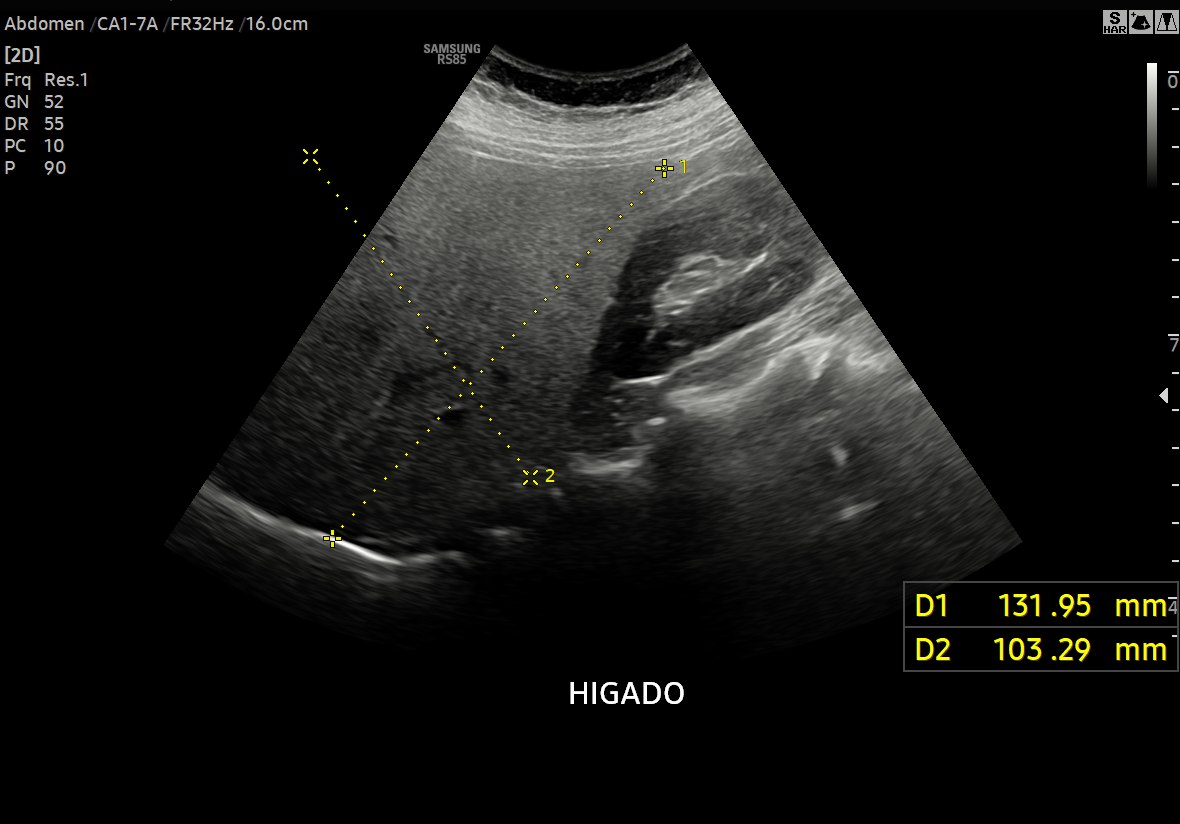

La ecografía de hígado en Lima de segunda opinión es un estudio especializado orientado a pacientes y médicos que requieren una reevaluación precisa de hallazgos hepáticos previamente informados o de diagnóstico incierto. En Diagnoimagen – Dr. Hubertino Díaz, aplicamos un enfoque avanzado basado en ecografía multiparamétrica, integrando modo B de alta resolución, Doppler hepático, elastografía (rigidez) y, cuando está indicado, técnicas de cuantificación de grasa hepática.

Este enfoque permite una mejor caracterización de patologías como hígado graso (esteatosis), fibrosis, cirrosis, hipertensión portal y lesiones focales hepáticas, reduciendo errores diagnósticos y aportando información clave para la toma de decisiones clínicas.

• Ecogenicidad y arquitectura hepática.

• Caracterización de lesiones focales.